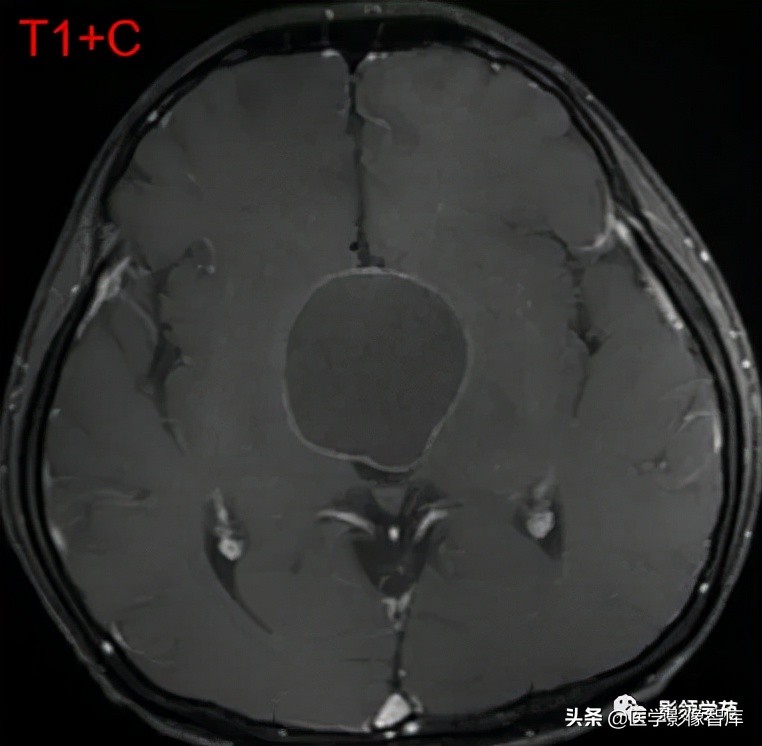

男 17岁,语言异常、视力减退、尿*禁失**、昏睡1月余。

鞍上池-第三脑室见一类圆形囊实性占位,边界清晰,内部以囊性长T1、长T2信号为主,信号均匀;另在囊下壁可见多发结节状实性病灶,呈乳头状向囊内凸起。

囊内实性病灶及囊壁明显强化,囊内容物无强化。视交叉受压向前移位,垂体可见,但垂体柄显示不清。中脑结构向后移位,中脑导水管通畅。

第三脑室明显变窄,双侧侧脑室、第四脑室外形正常。肿块邻近脑实质呈受压改变,关系清楚,无脑实质浸润及水肿信号。

(压迫视交叉、垂体柄、中脑;无梗阻性脑积水)